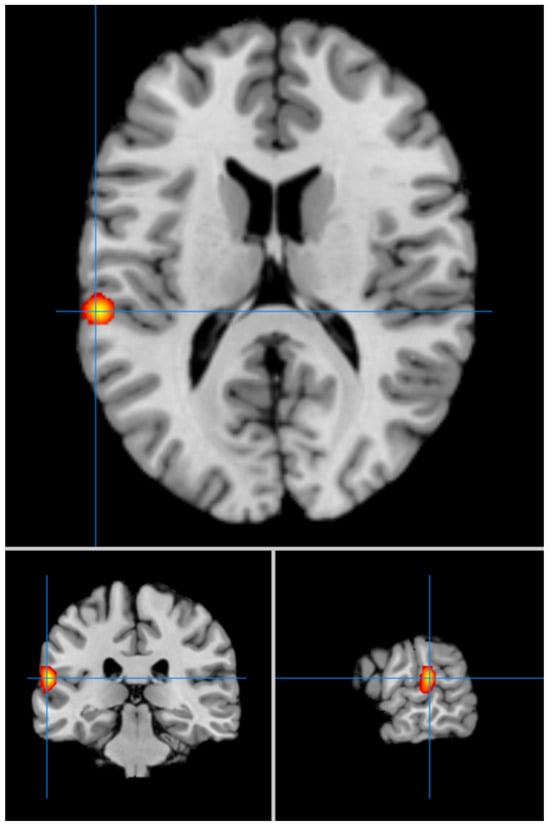

Our second analysis with cluster-level correction showed in LLD vs. HCs significant hyperfunctioning of the left superior temporal gyrus (BA 42) (MNI coordinates x = −60; y = −30; z = 14) (FWE p < 0.05) (Figure 2), and significant hypofunctioning of the right medial frontal gyrus (BA 8) (MNI coordinates x = 4; y = 32; z = 44) (Figure 3). We summarize the results of our meta-analysis in Table 2.

Figure 2.

Significant hyperfunctioning of the left superior temporal gyrus (MNI: −60, −30, 14) in LLD (FWE corrected).

The other most important result of our meta-analysis is the hyperfunctioning of the left STG (BA 42) in LLD vs. HCs. This area is physiologically involved in auditory stimuli processing [], visual speech perception [], being integrated with other regions within the mirror neuron system network (MSN) and possibly involved in social cognition and analysis of biological vs. non biological motion []. Our results are consistent with a recent study showing that decreased activation of the left STG in response to negative emotional expression is positively correlated with increases in positive affectivity in patients with LLD after eight weeks of mindfulness-based cognitive therapy []. Another study demonstrated increased regional homogeneity in this area in LLD patients compared to HCs [], further confirming the involvement of the left STG in the neuropathophysiology of LLD.